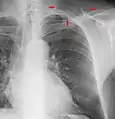

A chest radiograph with the angle parts of the ribs and some other landmarks labeled.

In the average person, the diaphragm should be intersected by the 5th to 7th anterior ribs at the mid-clavicular line, and 9 to 10 posterior ribs should be viewable on a normal PA inspiratory film. An increase in the number of viewable ribs implies hyperinflation, as can occur, for example, with obstructive lung disease or foreign body aspiration. A decrease implies hypoventilation, as can occur with restrictive lung disease, pleural effusions or atelectasis. Underexpansion can also cause interstitial markings due to parenchymal crowding, which can mimic the appearance of interstitial lung disease. Enlargement of the right descending pulmonary artery can indirectly reflect changes of pulmonary hypertension, with a size greater than 16 mm abnormal in men and 15 mm in women.[6]

Appropriate penetration of the film can be assessed by faint visualization of the thoracic spines and lung markings behind the heart. The right diaphragm is usually higher than the left, with the liver being situated beneath it in the abdomen. The minor fissure can sometimes be seen on the right as a thin horizontal line at the level of the fifth or sixth rib. Splaying of the carina can also suggest a tumor or process in the middle mediastinum or enlargement of the left atrium, with a normal angle of approximately 60 degrees. The right paratracheal stripe is also important to assess, as it can reflect a process in the posterior mediastinum, in particular the spine or paraspinal soft tissues; normally it should measure 3 mm or less. The left paratracheal stripe is more variable and only seen in 25% of normal patients on posteroanterior views.[7]

Localization of lesions or inflammatory and infectious processes can be difficult to discern on chest radiograph, but can be inferenced by silhouetting and the hilum overlay sign with adjacent structures. If either hemidiaphragm is blurred, for example, this suggests the lesion to be from the corresponding lower lobe. If the right heart border is blurred, than the pathology is likely in the right middle lobe, though a cavum deformity can also blur the right heard border due to indentation of the adjacent sternum. If the left heart border is blurred, this implies a process at the lingula.[8]